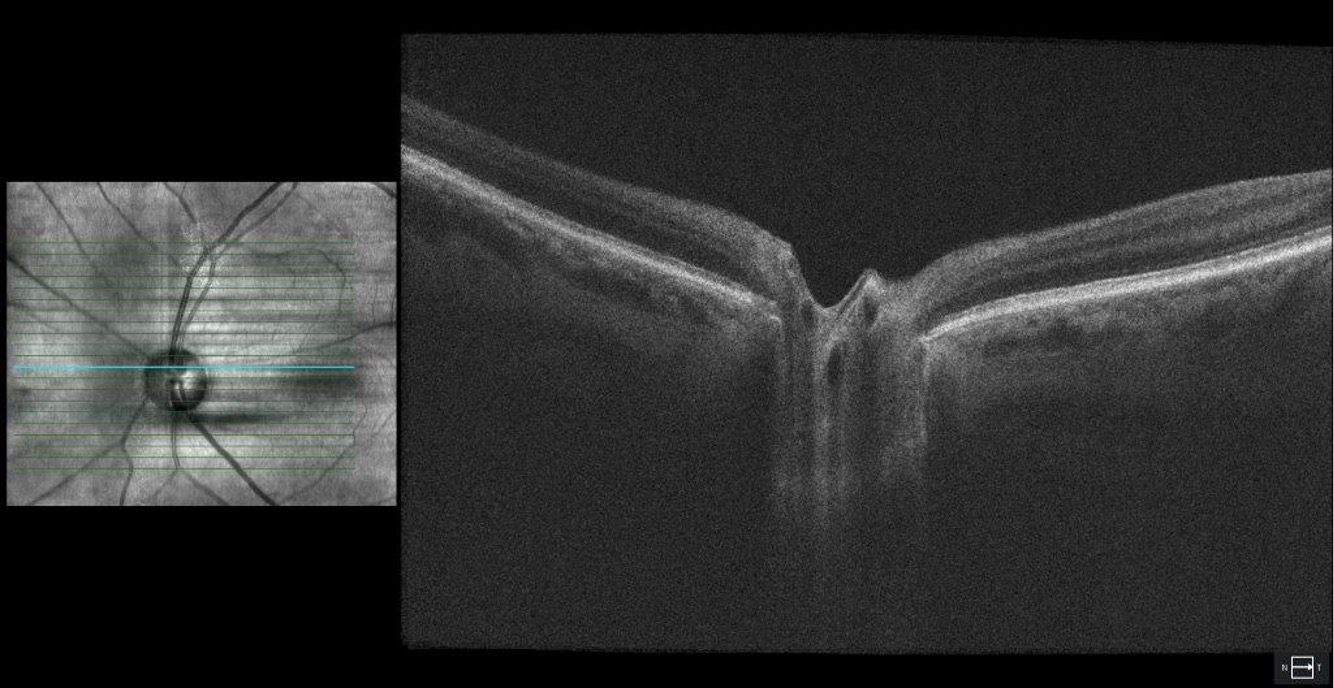

Optical coherence tomography (OCT) of the optic nerve head showing severe dropout of the ganglion cell complex (GCC) in both eyes. Average GCL thickness was 53 μm OD and 55 μm OS.

Figure 4. Optical coherence tomography (OCT) of the optic nerve head showing severe dropout of the ganglion cell complex (GCC) in both eyes. Average GCL thickness was 53 μm OD and 55 μm OS.

Figure 5. Optical coherence tomography (OCT) of the optic nerve head showing severe dropout of the ganglion cell complex (GCC) in both eyes.